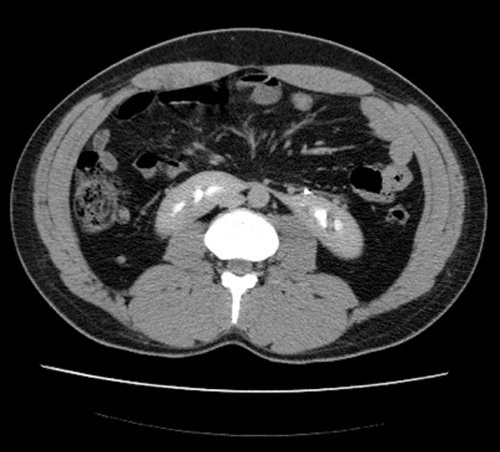

Case 1

CT urogram demonstrates contrast in both collecting systems and fused kidney inferiorly, consistent with a horseshoe kidney; one case in 400.

Fusion of the metanephric masses, usually at the lower pole. Inferior mesenteric artery obstructs ascent of the isthmus, leaving the isthmus at level of L3/4.

Pelviureteric junction (PUJ) obstruction (approximately 33%), stones (20%), undescended testes, hypospadias and Turner’s syndrome.